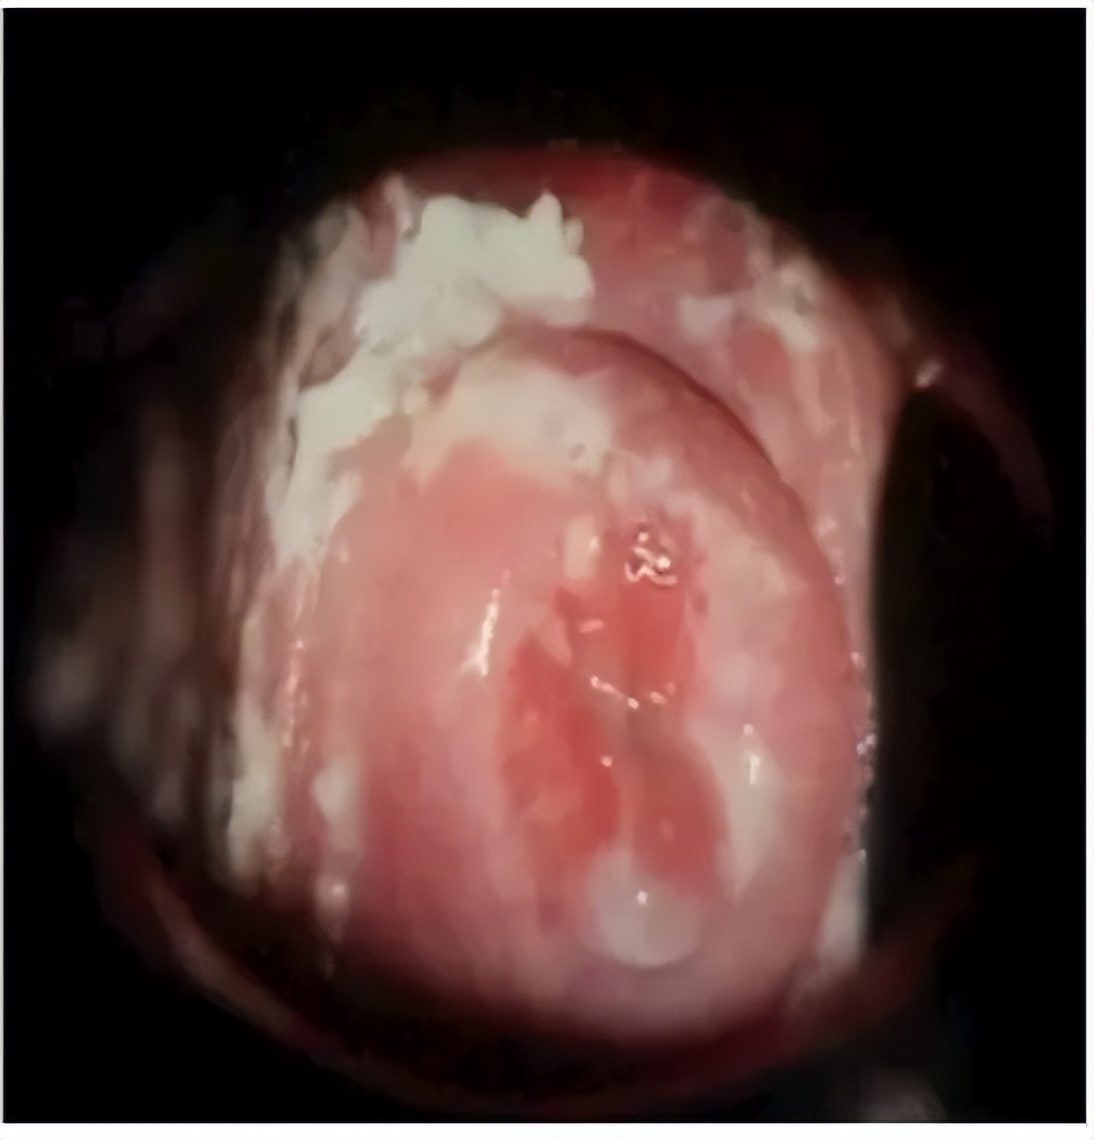

- 霉菌性阴道炎

这是孕期最常见的阴道炎,主要病原菌是以白色念珠菌为主的酵母菌,孕期阴道分泌物增多,外阴湿润,非常有利于霉菌繁殖和生长。

主要症状:白带呈豆腐渣样乳酪状,常伴有严重外阴瘙痒或灼痛。

- 滴虫性阴道炎

这也是比较常见的孕期阴道炎,是由阴道毛滴虫感染引起的,是一种传染性疾病。

主要症状:白带呈稀薄脓性、黄绿色、泡沫状,外阴瘙痒,伴有尿道感染时可有尿痛、尿频等。

- 细菌性阴道炎

它是由阴道正常菌群失调所致的一种混合感染。

主要症状:白带呈灰白色、稀薄,有鱼腥臭味,伴轻度外阴瘙痒。